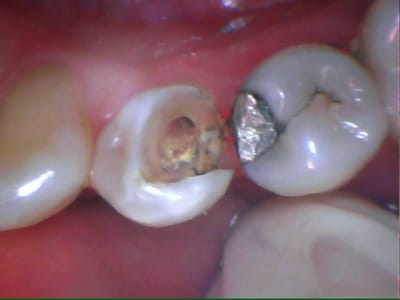

Inlay réalisable sur 24 et 34 ?

Est-ce que le collage suffirait à maintenir les parois ?

Le choix thérapeutique pris a été très classique.

Arnaud Go écrivait:

> Onlay réalisable sur 24 et 34 ?

oui

> Est-ce que le collage suffira à maintenir les parois ?

non, je préférai les recouvrir sur 1.5 mm par l'onlay

Inlay tu avais corrigé tout seul...

Tu le transformes en onlay par recouvrement occlusal pour éviter l'éclatement. Tu es conservateur mais la transition dent-prothèse sera en V donc visible pour ceux qui n'ont pas tous la chance d'avoir ton prothésiste et/ou ton talent.

Je ne suis pas sûr que je le ferais sur moi, ou alors un retour V jusqu'en cervical mais c'est presque de la couronne.

Quel système de collage a eu ta faveur ?